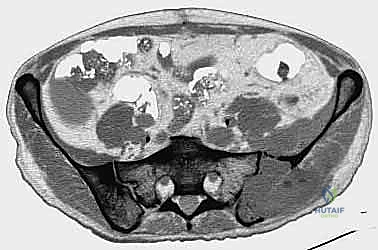

- التصوير المقطعي المحوسب (CT Scan): يقدم صوراً ثلاثية الأبعاد تُظهر بدقة متناهية مدى تدمير القشرة العظمية، وهو الفحص الأهم للتخطيط الجراحي وتحديد خطر حدوث الكسور المرضية.

- المسح الذري للعظام (Bone Scan) أو التصوير البوزيتروني (PET-CT): لتحديد ما إذا كان هناك انتشار للسرطان في عظام أخرى من الجسم، ولتقييم النشاط الأيضي للورم.

- الخزعة (Biopsy): في حال كان الورم في الحوض هو أول ظهور للسرطان (سرطان أولي مجهول المصدر)، يتم أخذ عينة من الأنسجة تحت إرشاد الأشعة المقطعية لتحديد نوع الخلايا السرطانية بدقة.